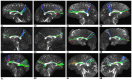

The existence of the superior fronto-occipital fasciculus (SFOF) in the human brain remains controversial. The aim of the present study was to clarify the existence, course, and terminations of the SFOF. High angular diffusion spectrum imaging (DSI) analysis was performed on six healthy adults and on a template of 842 subjects from the Human Connectome Project. To verify tractography results, we performed fiber microdissections of four post-mortem human brains. Based on DSI tractography, we reconstructed the SFOF in the subjects and the template from the Human Connectome Project that originated from the rostral and medial parts of the superior and middle frontal gyri. By tractography, we found that the fibers formed a compact fascicle at the level of the anterior horn of the lateral ventricle coursing above the head of caudate nucleus, medial to the corona radiate and under the corpus callosum (CC), and terminated at the parietal region via the lower part of the caudate nucleus. We consider that this fiber bundle observed by tractography is the SFOF, although it terminates mainly at the parietal region, rather than occipital lobe. By contrast, we were unable to identify a fiber bundle corresponding to the SFOF in our fiber dissection study. Although we did not provide definite evidence of the SFOF in the human brain, these findings may be useful for future studies in this field.